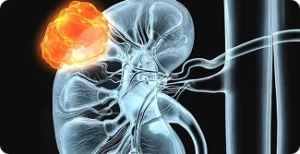

dos tumores renais pequenos podem ser tratados com cirurgia robótica, preservando o rim e mantendo alta segurança oncológica.

A nefrectomia parcial robótica é uma cirurgia minimamente invasiva para remover tumores renais, preservando o órgão. O cirurgião usa um console 3D para controlar braços robóticos inseridos por pequenas incisões.

Cirurgia para retirada parcial ou total do rim afetado por tumor, realizada com alta precisão robótica e foco em preservar o máximo possível da função renal.